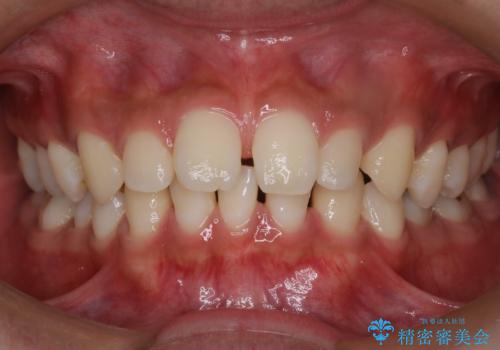

【インビザライン】空隙歯列の矯正

- 前歯の隙間を主訴に来院されました。

なるべく目立たない治療を希望されましたので、インビザラインにて治療を行なっております。

単純に前歯の隙間の閉鎖をしてしまうと、前歯に早期接触が生まれ、臼歯が噛まなくなってしまいます。適切な治療計画を立てることで、噛み合わせも良好な結果を得ることができました。